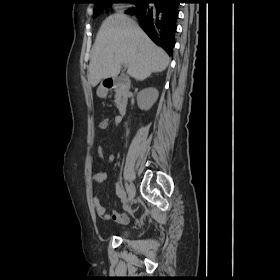

A CT abdomen revealed a left adrenal cortical tumor.

Her abdominal X-ray also reveals a right renal stone although she never complained of renal colic.

Clinician advised against surgery because she was not in pain. Her TSH is normal. A CT abdomen revealed a left adrenal cortical tumor. Diagnosis of pri. aldosteronism was made. Patient is hypertensive since 1995 since her second childbirth. Now BP is normal with medication. She is nondiabetic. Pt. advised to report her Ca2+ and K+ lvl. monthly. Pt. acq. the habit of eating paan (beetle leaf) from her mother in 2011 when she came to stay with her. Used to eat 3-4 paans a day. Stopped in 2013 after Dr. advised against it.

PATIENT'S HISTORY: The patient is a 60-year-old housewife. In 2013, she had an episode of probable stroke followed by nausea, vomiting, diarrhea, weakness, fatigue with loss of appetite, and insomnia. Her legs felt numb. She lost sensation around neck. Had to be admitted to a nursing home. Diagnosis of hypocalcemia and hypokalemia was made. Got discharged after 5 days when k+ and Ca2+ lvl. returned to normal via i.v infusion. For 2 yrs she was fine. In 2015, due to diarrhea and fatigue she got admitted to a Nursing home and stayed there for 7 days. Ca2+ and K+ lvl. was falling, so restored via i.v infusion. This time hypernatremia was also detected. Discharged after her conditions improved. But 2 days later, again due to severe diarrhea had to be admitted to a Nursing home for 19 days. During her stay USG of abdomen, colposcopy and chest X-ray was done. USG detected a large renal calculus measuring 22mm in rt. kidney. Sx was recommended. Pt went to Bhopal for a second opinion.